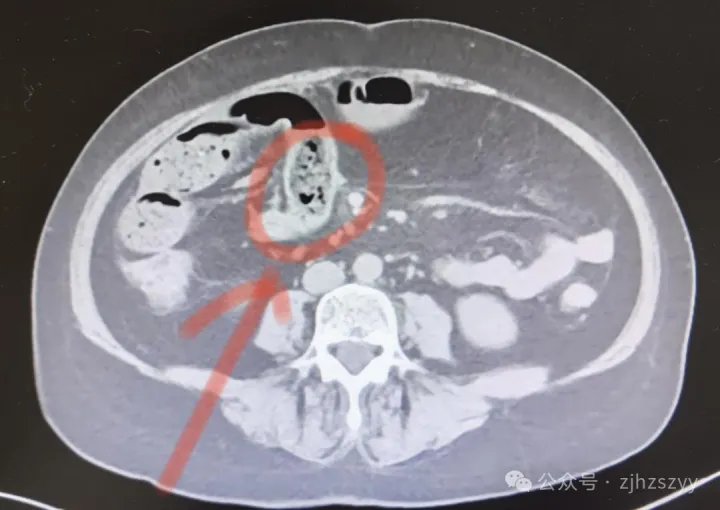

普外科医生接诊后,为宋女士安排了腹部CT检查,检查结果提示:小肠肠梗阻。医生立即将宋女士收治入院,为她进行了禁食、补液、胃肠减压等保守治疗,希望能通过非手术方式解除梗阻。

然而,宋女士的病情在24小时内急转直下,复查的腹部增强CT显示,肠梗阻不仅没有缓解,反而较前加重,并且出现了腹腔积液。

医生解释,腹腔积液是一个危险的信号,通常意味着梗阻的肠管可能因为过度膨胀、缺血,出现了渗漏甚至即将坏死的迹象。如果再不干预,可能会导致肠道穿孔、弥漫性腹膜炎,甚至危及生命。